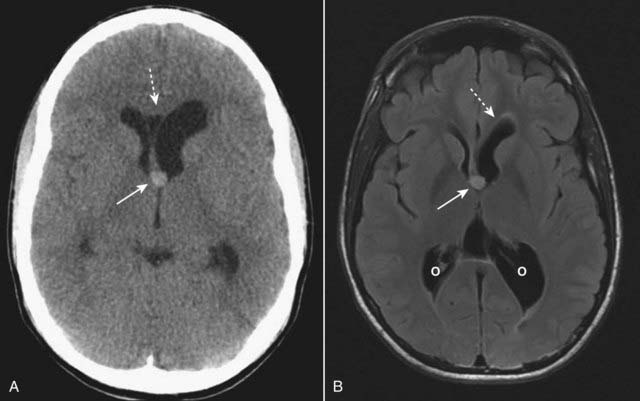

image

Figure 25-24 Colloid cyst of the 3rd ventricle, CT and MRI.

A colloid cyst is a rare, benign lesion of the 3rd ventricle that can cause obstructive hydrocephalus. A, There is a hyperdense mass in the anterior aspect of the 3rd ventricle (solid white arrow) causing asymmetric obstruction of the left foramen of Monro compared to the right (dotted white arrow). B, On this T2-like sequence, the lesion has increased signal (solid white arrow) and is causing dilatation of the frontal (dotted white arrow) and occipital (O) horns of the lateral ventricle.